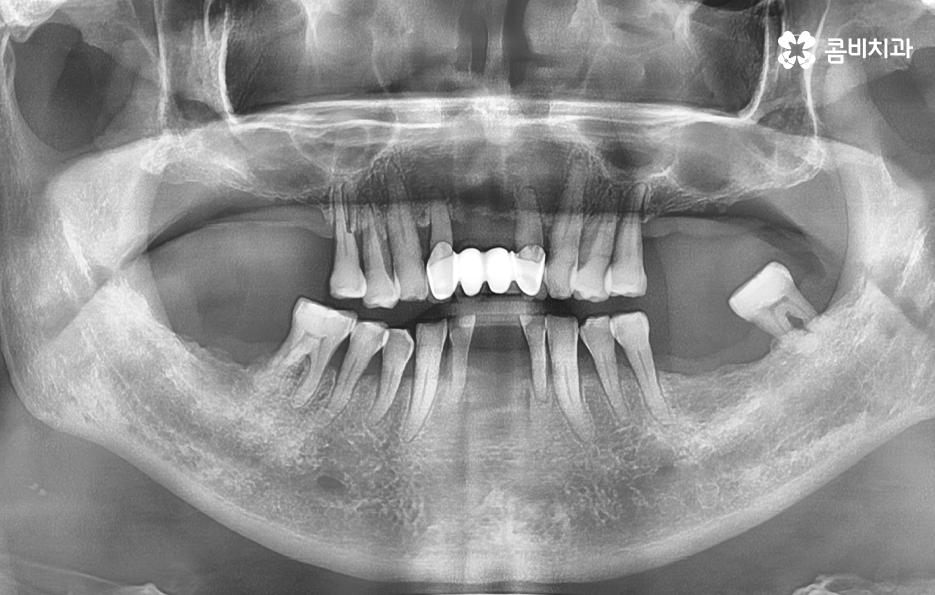

그 중에서도 치주염으로 인해 위에 보시는 사례 사진처럼 잇몸은 내려앉고 치아 뿌리가 외부에 상당 부분 드러나는 경우에는 우선 일상에서 치아가 무척이나 시리고 통증을 느끼게 되며 치주염이 결국 잇몸 뼈를 녹게 만들어서 치아 뿌리가 흔들리고 결국 발치하게 되는 경우가 많아요

50대에 관리가 잘 안되던 치주질환은 결국 60대에 이르러 한꺼번에 여러 치아를 상실하게 되고 그에 따라 임플란트도 여러개를 식립해야 하는 사례가 많다는 점을 주목하실 필요가 있는데요

치주염은 충치 이상으로 치아를 상실하게 만드는 대표적 원인이며 치주염은 주변 잇몸 뼈에도 악화되고 잇몸 뼈를 녹인다는 점에서도 임플란트를 해야할 시점이 되면 잇몸 뼈의 부족으로 인한 뼈이식을 받게 되는 경우가 많을 거예요